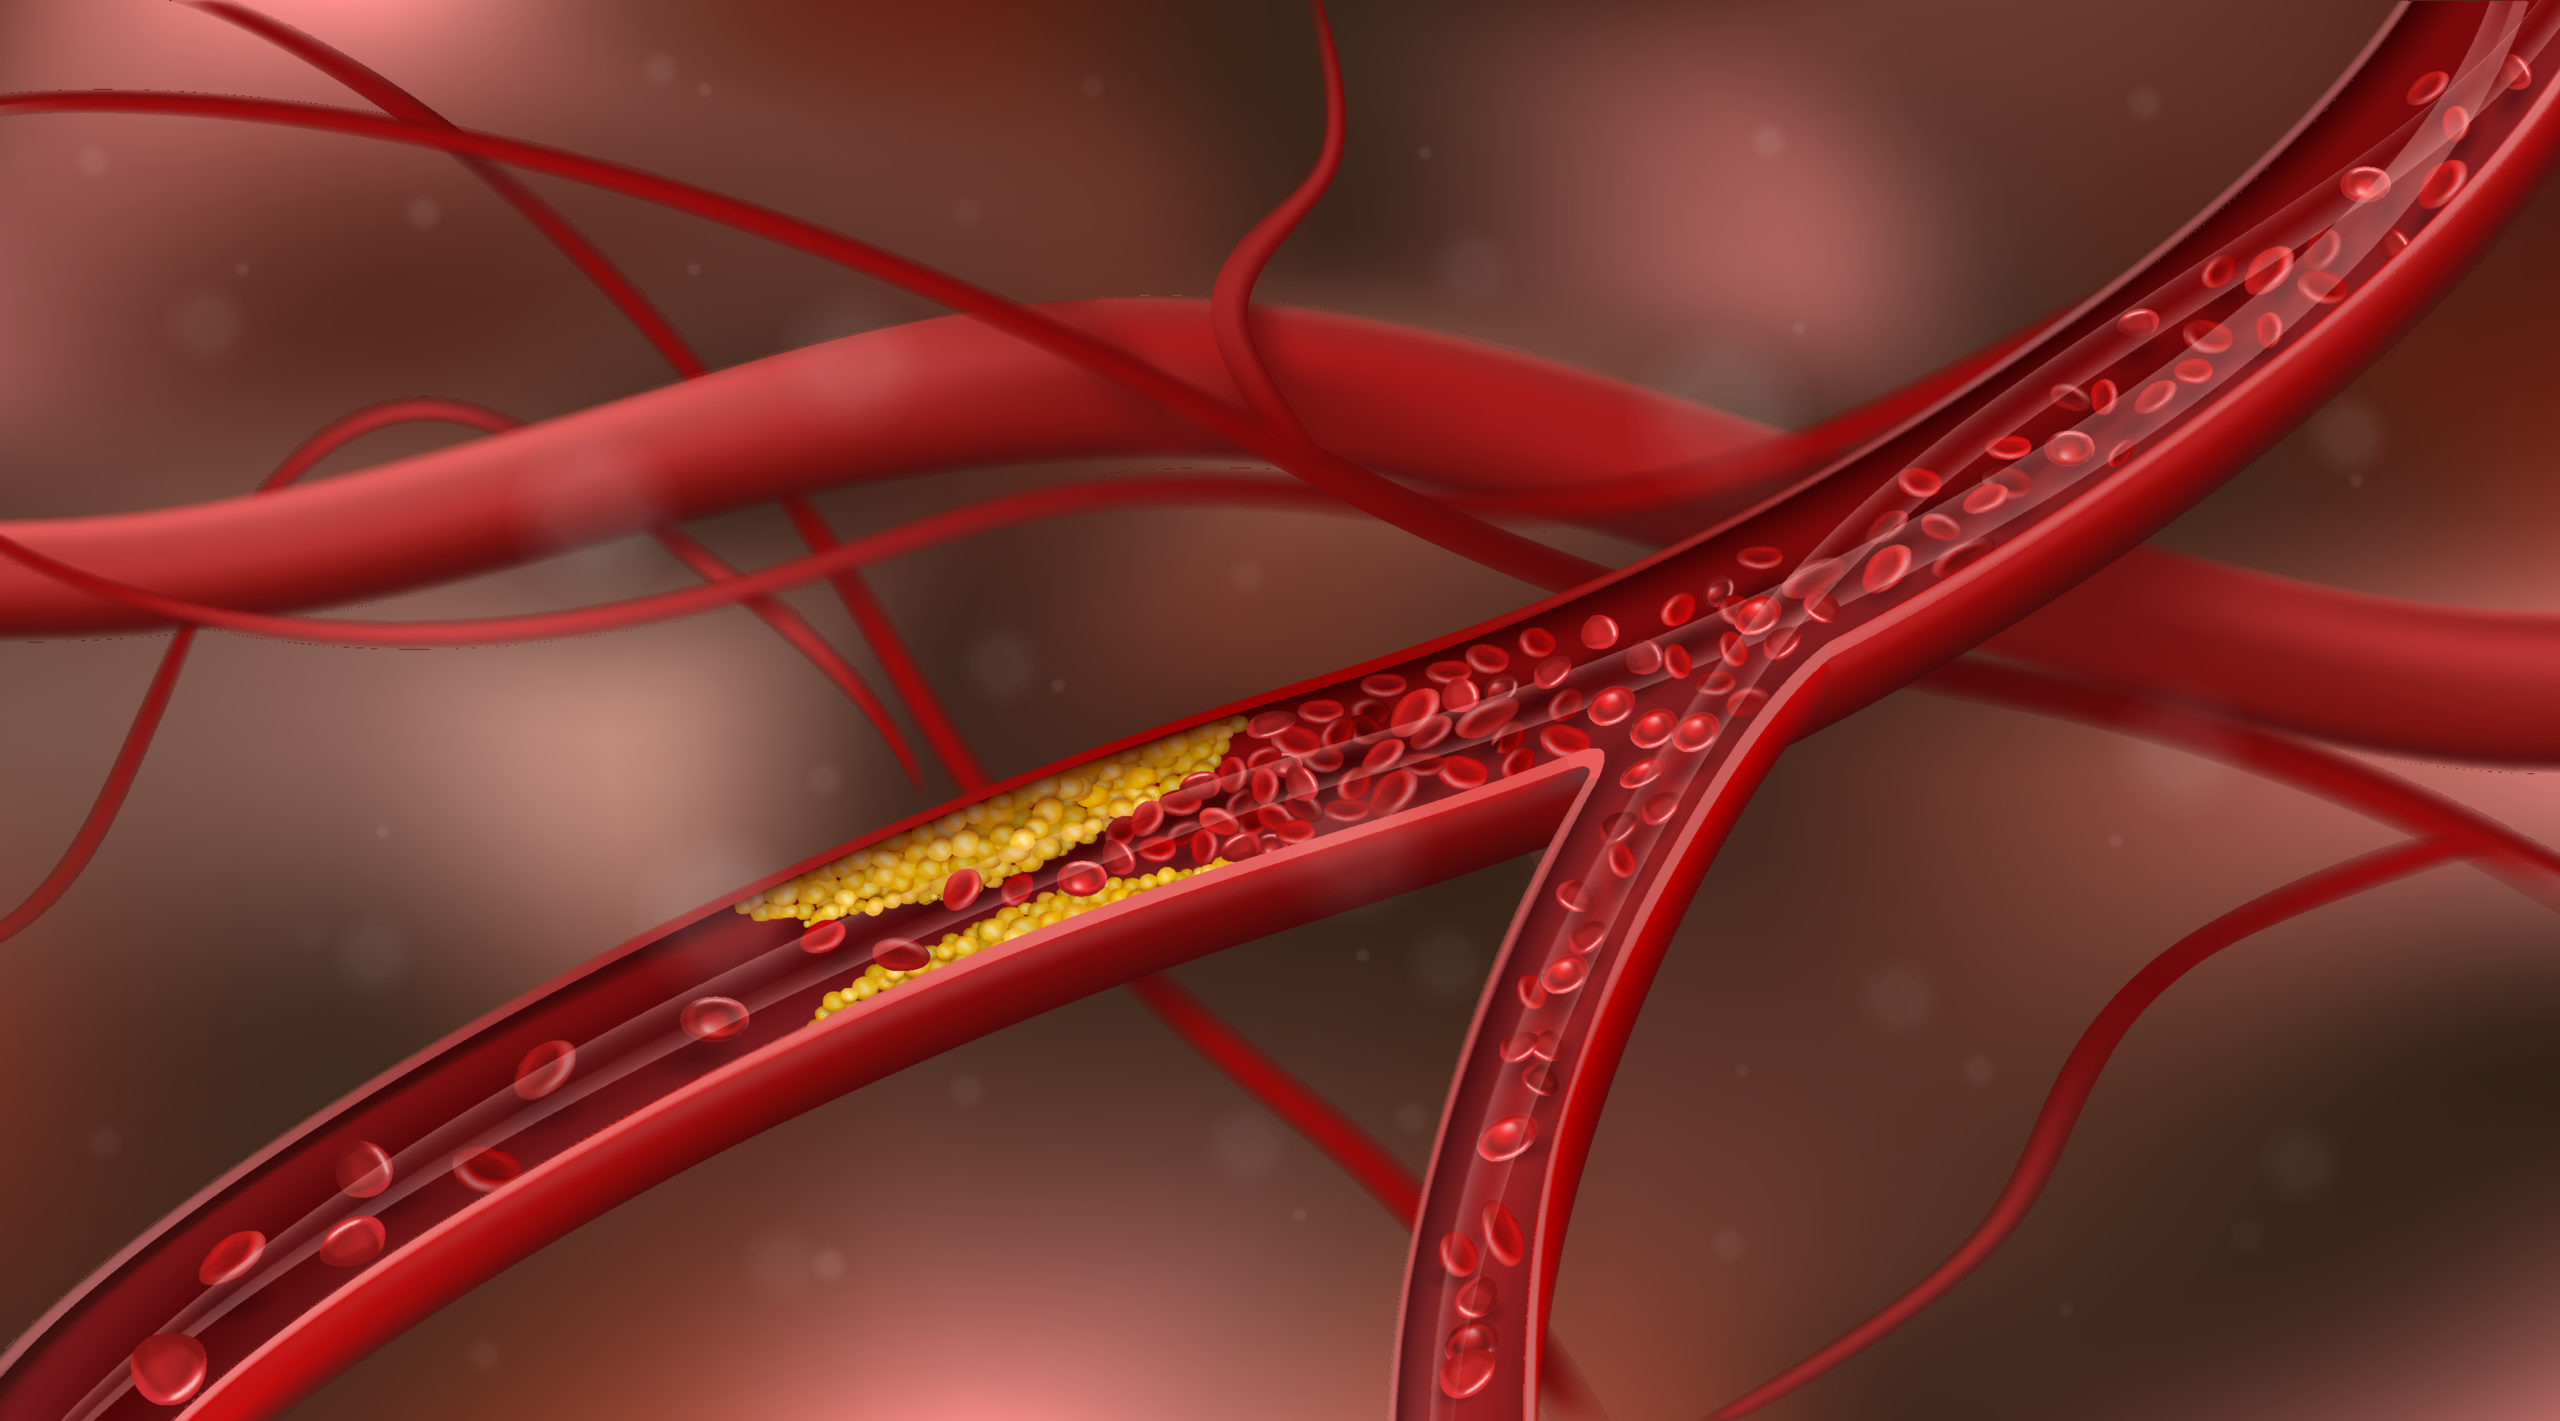

Peripheral artery disease (PAD) is a significant contributor in cardiovascular morbidity and mortality; However, ...

Galectin-3 (Gal-3) is a biomarker associated with fibrosis and vascular inflammation and has been linked to chronic ...

Investigators reported that atrial fibrillation (AFib) increased the risk of mortality, stroke, and heart failure in ...